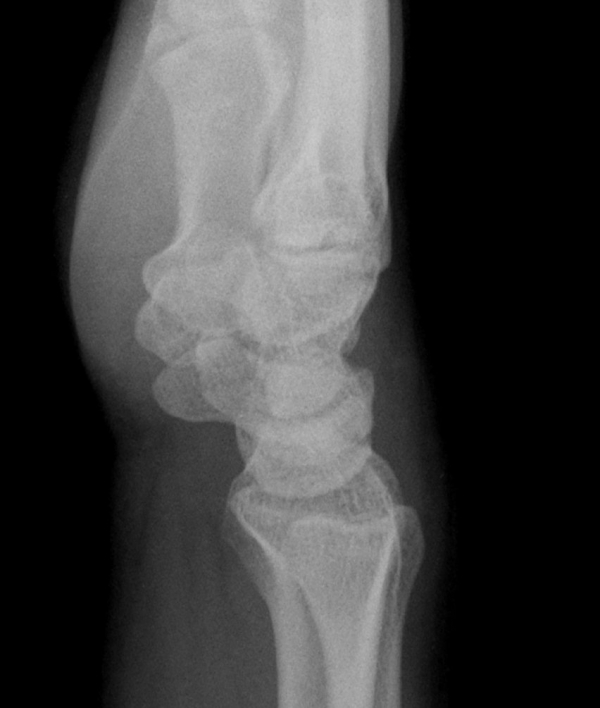

¹æ»ç¼± °Ë»ç : ƯÀÌ ¼Ò°ß ¾ø(»çÁø 5, 6).